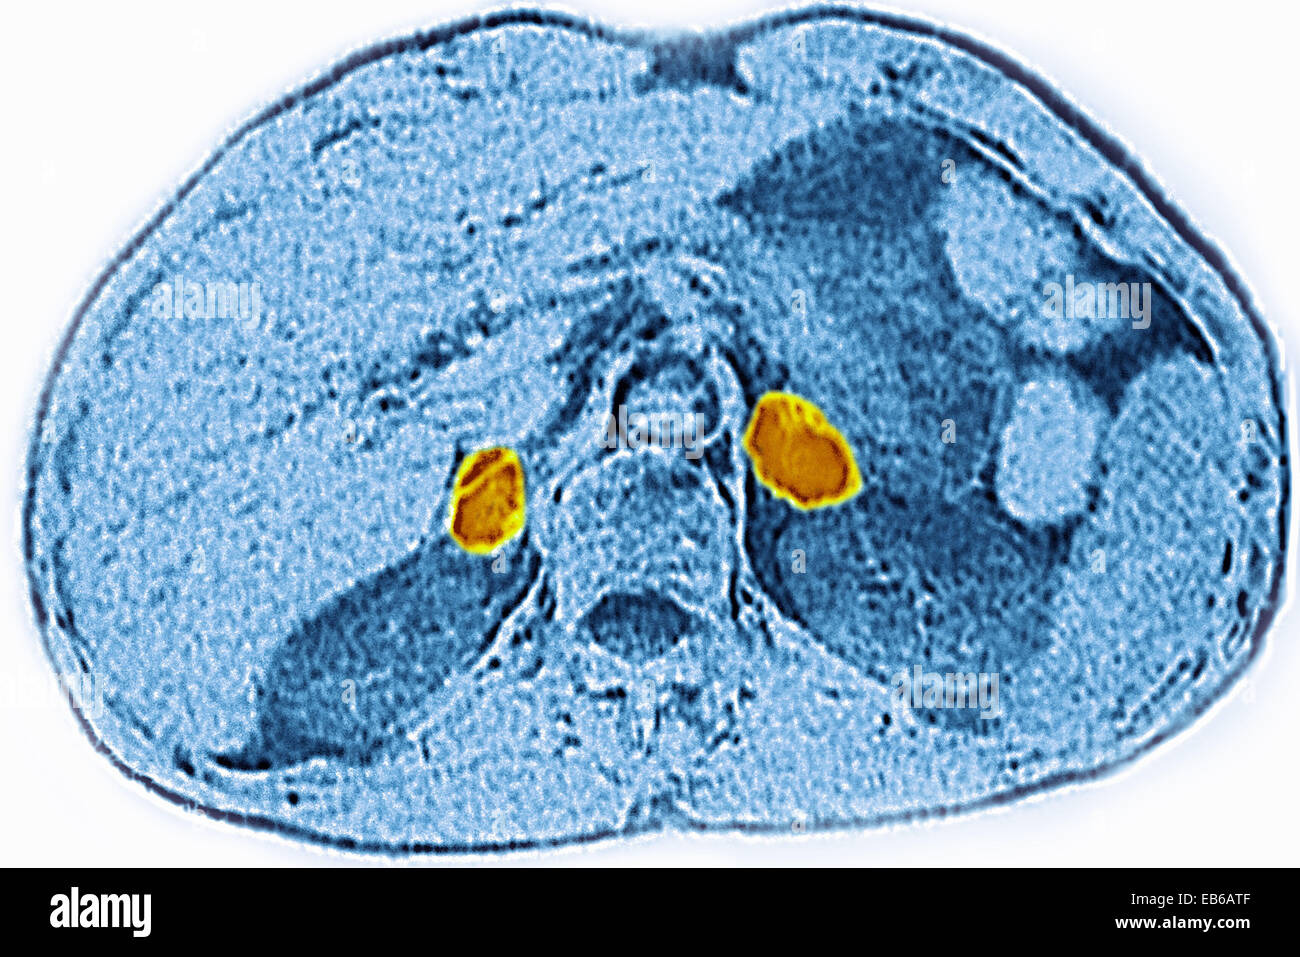

From www.alamy.com

ADRENAL GLAND, CT SCAN Stock Photo Alamy Adrenal Gland Scan Procedure different lesions have different treatment options and clinical prognoses, so it is of great clinical value. During this minimally invasive procedure, a long, thin instrument with a camera attached (a. a ct scan of the adrenals is a medical imaging procedure used to evaluate the adrenal glands, which are two small glands located on top of each kidney.. Adrenal Gland Scan Procedure.